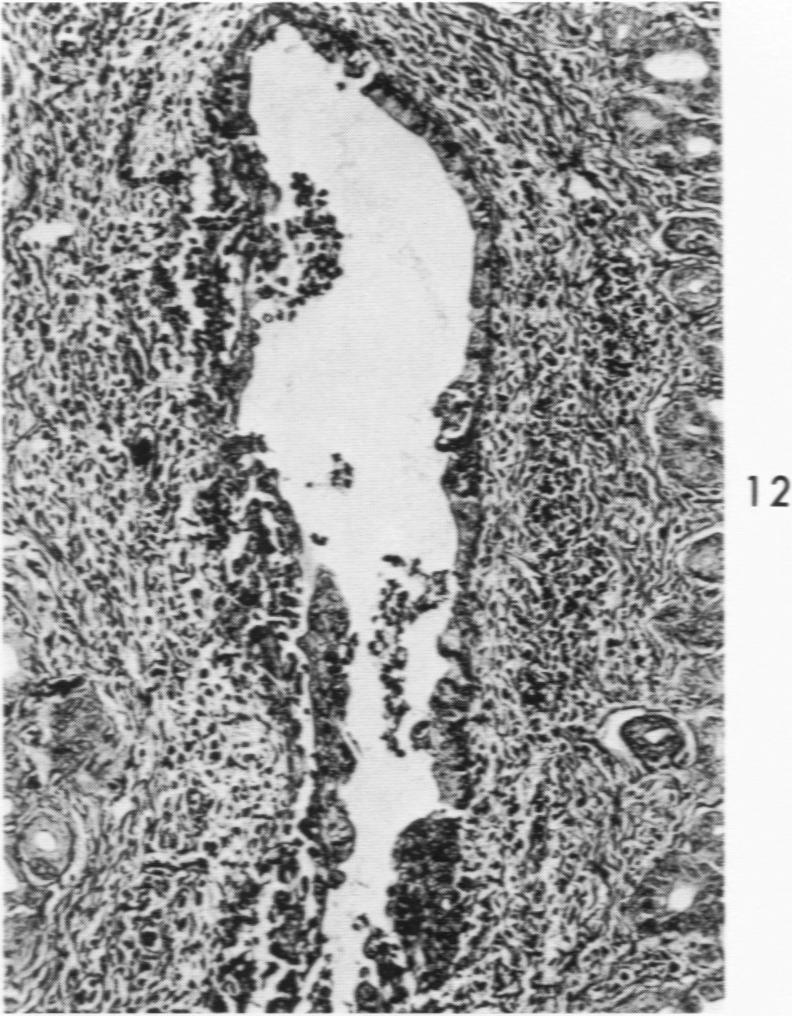

Acute Newcastle disease virus infection following intranasal inoculation of chicks with a mesogenic strain of the virus produced a localized infection of the middle turbinate which was histologically demonstrable 18 hours after inoculation. There was destruction of mucous cells of individual acini in the under surface of the middle turbinate, and the infection rapidly spread to ciliated and goblet cells and to neighboring acini. By day 2 there was simultaneous remodeling of the mucosa, continued destruction and inflammatory infiltration and frequent loss of cartilage basophilia. By day 3 polymorphonuclear cells almost disappeared, epithelial mitoses commenced, and lymphocyte infiltration intensified; the plasma cells normally present along the lateral nasal gland ducts were often destroyed, very occasionally the glands themselves were destroyed. By days 5 and 6 inflammation greatly decreased, and by day 8 the mucociliated epithelium was essentially normal. The infection is sequentially comparable to acute mild rhinitis of man.

用新城疫病毒的中等毒力株经鼻腔接种雏鸡后,会引发急性感染,在接种后18小时可通过组织学方法证实中鼻甲出现局部感染。中鼻甲下表面单个腺泡的黏液细胞遭到破坏,感染迅速蔓延至纤毛细胞、杯状细胞及相邻腺泡。到第2天,黏膜同时发生重塑,破坏和炎性浸润持续存在,软骨嗜碱性常常丧失。到第3天,多形核细胞几乎消失,上皮细胞开始有丝分裂,淋巴细胞浸润加剧;沿鼻外侧腺管通常存在的浆细胞常被破坏,腺管本身偶尔也会被破坏。到第5天和第6天,炎症大为减轻,到第8天,黏液纤毛上皮基本恢复正常。这种感染过程与人的急性轻度鼻炎有相似之处。